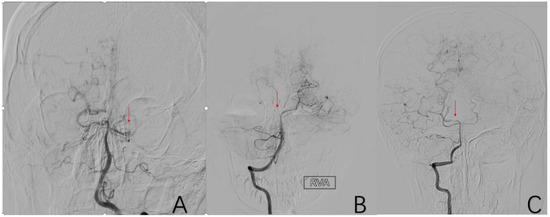

2.3.7. Factor 2 A1 Stenosis

2.3.8. Factor 3 M1 Stenosis

2.3.9. Factor 4 PCA Anomaly